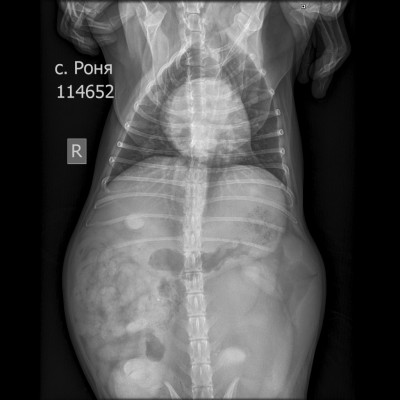

Москва, цвергшнауцер Роня, 6 лет

Рентген в двух проекциях и бак посев из раны